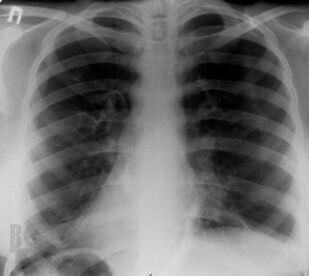

Монография посвящена актуальной проблеме редких (орфанных) заболеваний легких у детей, включающих как собственно наследственные, врожденные, интерстициальные и другие редкие заболевания легких, так и легочные поражения при разнообразной другой редкой патологии. В книге обобщены современные мировые данные, а также многолетний опыт сотрудников клиники пульмонологии Московского НИИ педиатрии и детской хирургии (ныне – НИКИ педиатрии им. акад. Ю.Е. Вельтищева РНИМУ им. Н.И.Пирогова). Для работы над рядом глав привлечены ведущие специалисты из других учреждений страны. Монография адресована детским пульмонологам и аллергологам, практикующим педиатрам и врачам общей практики, другим специалистам, интересущимся орфанной патологией.